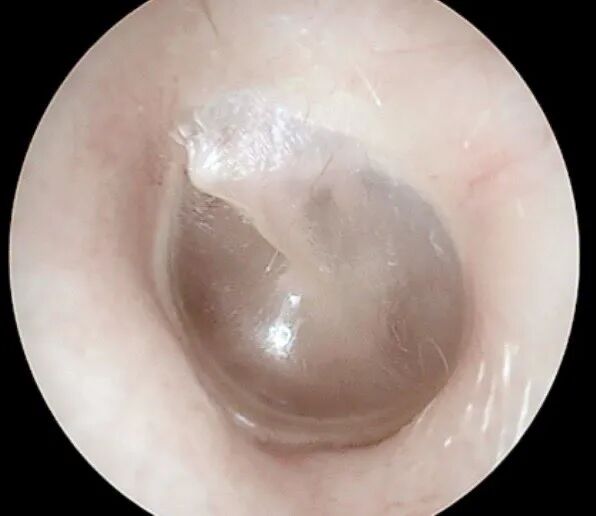

我们可以把耳朵简单分为外耳、中耳和内耳。中耳是一个包含听小骨的含气空腔,它有一层重要的门户——鼓膜,用来隔绝外部,保护内部结构。

正常鼓膜